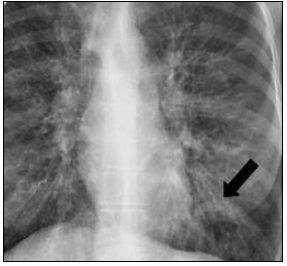

Considere o seguinte achado no exame de imagem pulmonar:

É correto afirmar que trata-se de